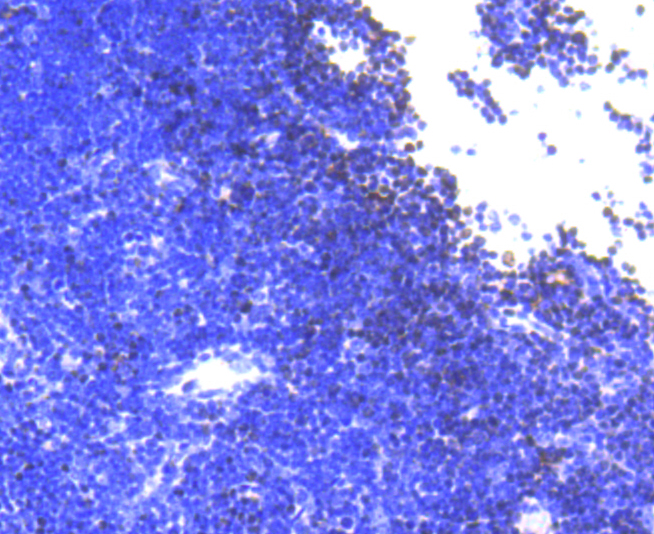

Immunohistochemical analysis of paraffin-embedded rat spleen tissue using anti-SATB1 antibody. Counter stained with hematoxylin.

Immunohistochemical analysis of paraffin-embedded mouse thymus tissue using anti-SATB1 antibody. Counter stained with hematoxylin.